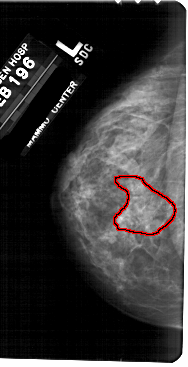

A_1724_1.LEFT_MLO

FILE: A_1724_1.LEFT_MLO.OVERLAY

TOTAL_ABNORMALITIES 1

ABNORMALITY 1

LESION_TYPE CALCIFICATION TYPE PLEOMORPHIC-FINE_LINEAR_BRANCHING DISTRIBUTION SEGMENTAL

ASSESSMENT 4

SUBTLETY 3

PATHOLOGY MALIGNANT

TOTAL_OUTLINES 1

BOUNDARY